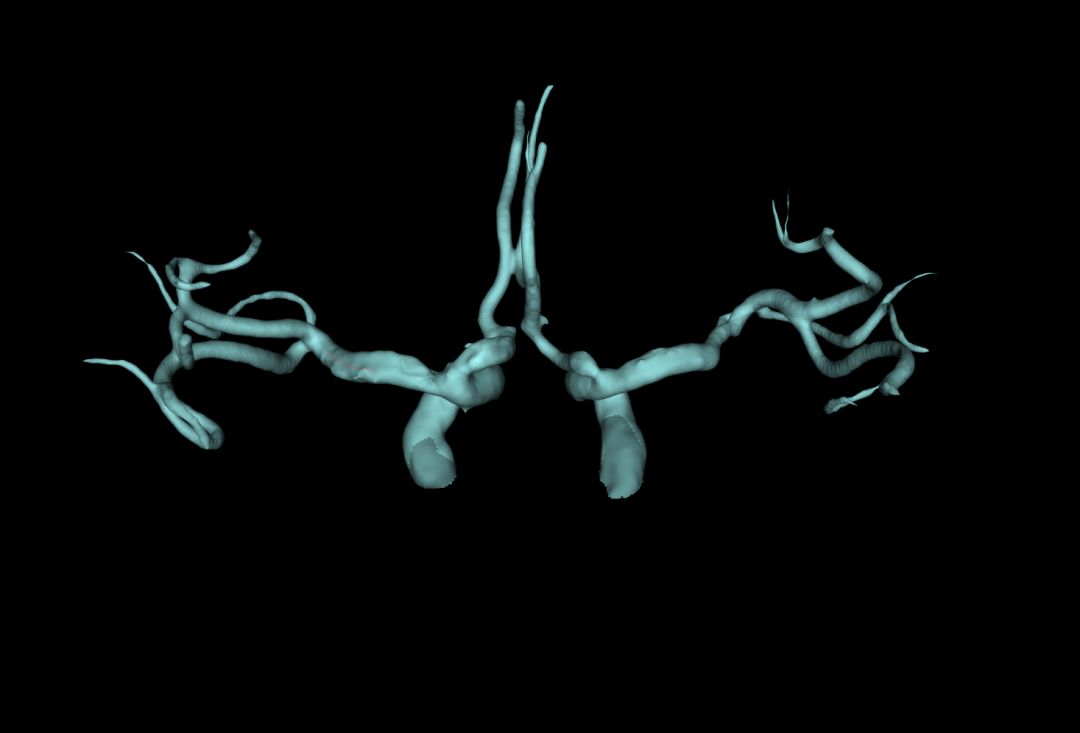

2006 年,法国的放射科医生Klein用1.5 T磁共振(MRI)完成大脑中动脉的血管壁成像之后,高分辨磁共振(HRMRI)的颅内血管成像技术引起广泛关注。

在2009年,加拿大的Swartz和中国北京协和医院的李明利医生先后用3.0 T磁共振进行了颅内血管成像,获得更高的成像质量,使其具备了观察者间和观察者内的可重复性。

从此,HRMRI的用途不断获得开拓,它不仅仅用于诊断颅内动脉粥样硬化和风险分层,也用于其他颅内动脉疾病的诊断,如夹层、血管炎、Moyamoya病、可逆性血管收缩综合征等。